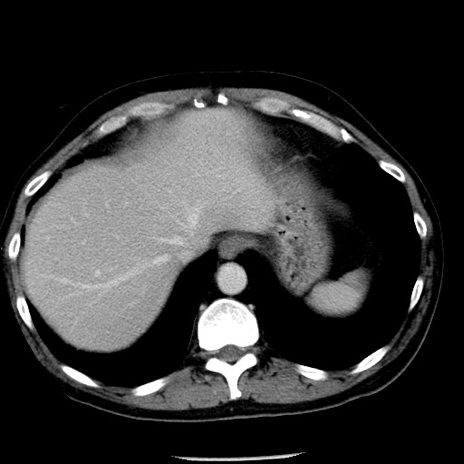

冠状断像

【症例】40歳代男性

【現病歴】2日前から胃痛あり。徐々に周期的な激痛に変化した。本日になっても激痛があるため受診。

【身体所見】意識清明、BT 38-39℃台あり、腹部:膨満、やや硬、右下腹部に圧痛あり。

【データ】WBC 8500、CRP 23.26